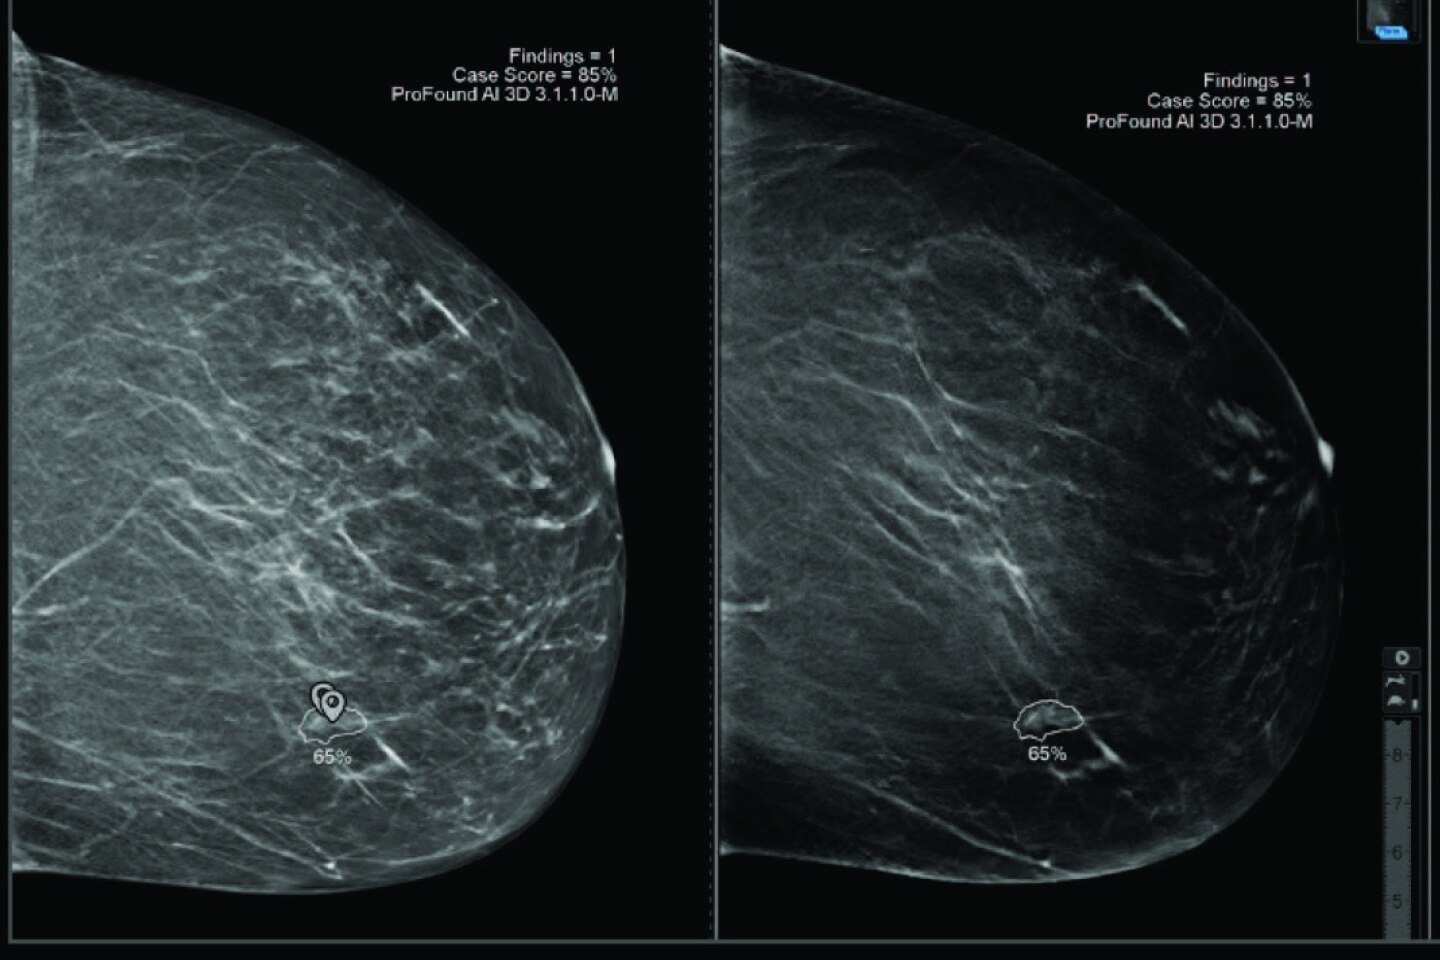

ProFound AI® for DBT

Trained with one of the largest available 3D image datasets, ProFound AI provides radiologists with crucial information, such as lesion Certainty of Finding and Case Scores, which assists in prioritizing caseload, clinical decision-making and may help to reduce physician burnout3.

iCAD reader study shows that reading with ProFound AI:

• Increases reader sensitivity by 8%. 4

• Increases reader specificity by 6,9%. 4

• Decreases reading time by up to 52% compared to without. 4

Easy navigation between the V-Preview and the slices containing the AI markers.